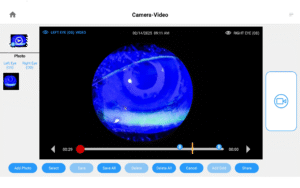

Photos & Videos. Clinical Documentation. Patient Education. Reimbursement.

Illuminate your exams and transform patient engagement like never before. When patients see detailed images of their eyes, they gain a deeper understanding of their health and recognize the importance of compliance and follow-up care. Throughout development, our team saw firsthand the profound impact of imaging in the clinic—watching patients smile, express genuine appreciation, and embrace their health journey. That unforgettable experience remains the most rewarding part of our work.

Opteon was born and developed in the clinic, meticulously tested, and perfected through countless hours to ensure that it flows with your exam routine — delivering unmatched reliability and efficiency.